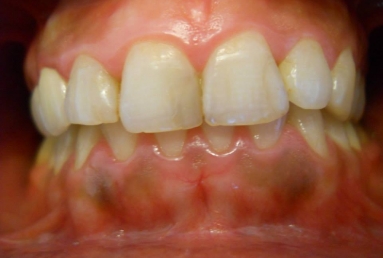

Porcelain veneers on all four upper incisors

Before treatment : inappropriate composite fillings on all four upper incisors, the patient will receive four porcelain veneers.